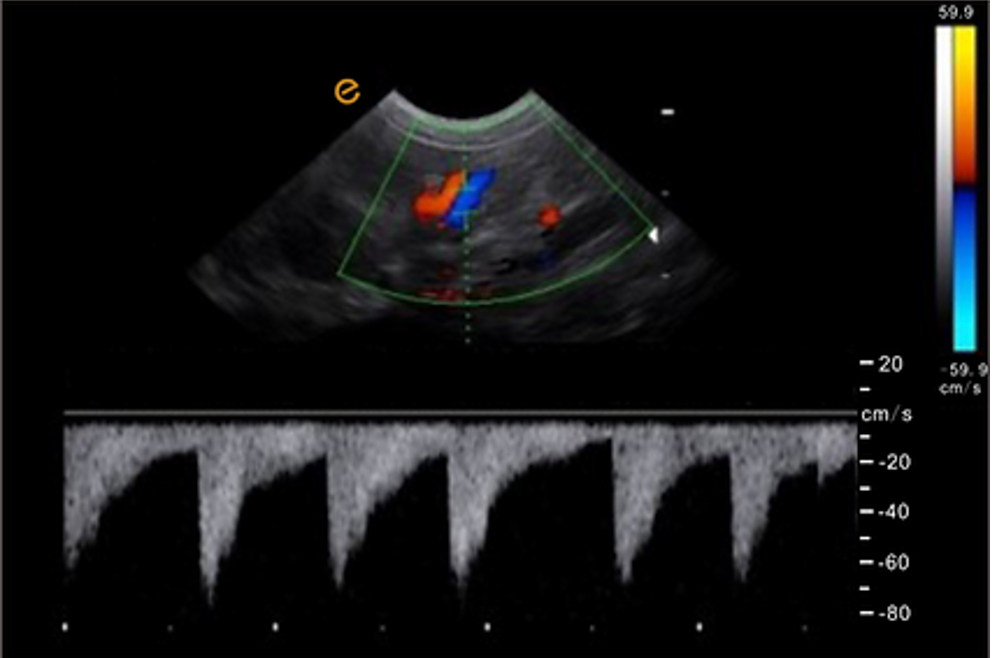

การสกรีนแบบไดนามิกแบบเรียลไทม์สามโหมดพร้อมกัน รองรับการตรวจแบบไดนามิกพร้อมกันใน 3 โหมด ได้แก่ B-Mode, Color Flow Mapping (CFM), และ Pulsed Wave Doppler (PW) เพื่อการวินิจฉัยที่แม่นยำและครอบคลุมในเวลาเดียวกัน |